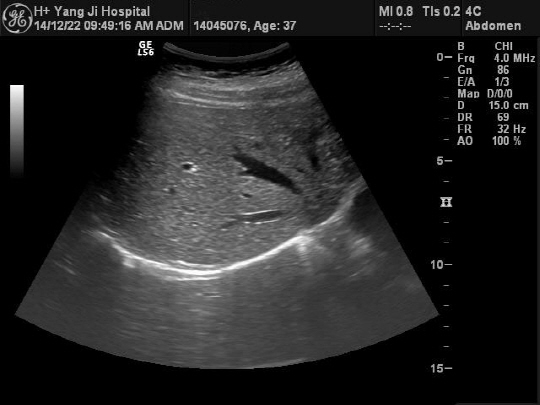

간 질환 예측을 위해 시행되는 검사는 혈액검사와 초음파 검사가 일반적이다. 혈액검사는 간의 염증반응, 바이러스 보균상태, 간 기능의 이상여부 등을 파악할 수 있다. 초음파검사는 간 모양의 변화를 확인하기 위해 실시된다. 간경변증 진행여부나 간 종양의 생성여부 등을 평가할 수 있다. 정진용 과장은 "혈액검사와 초음파검사를 모두 시행하는 것이 좋지만 무엇보다 의료진과 소통하면서 증상에 맞는 검사법을 적용해야 한다"고 설명했다.

◇간 초음파